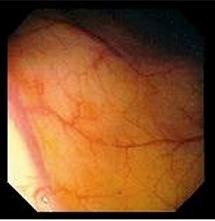

Colosscopie du colon : Image

macroscopique normale |